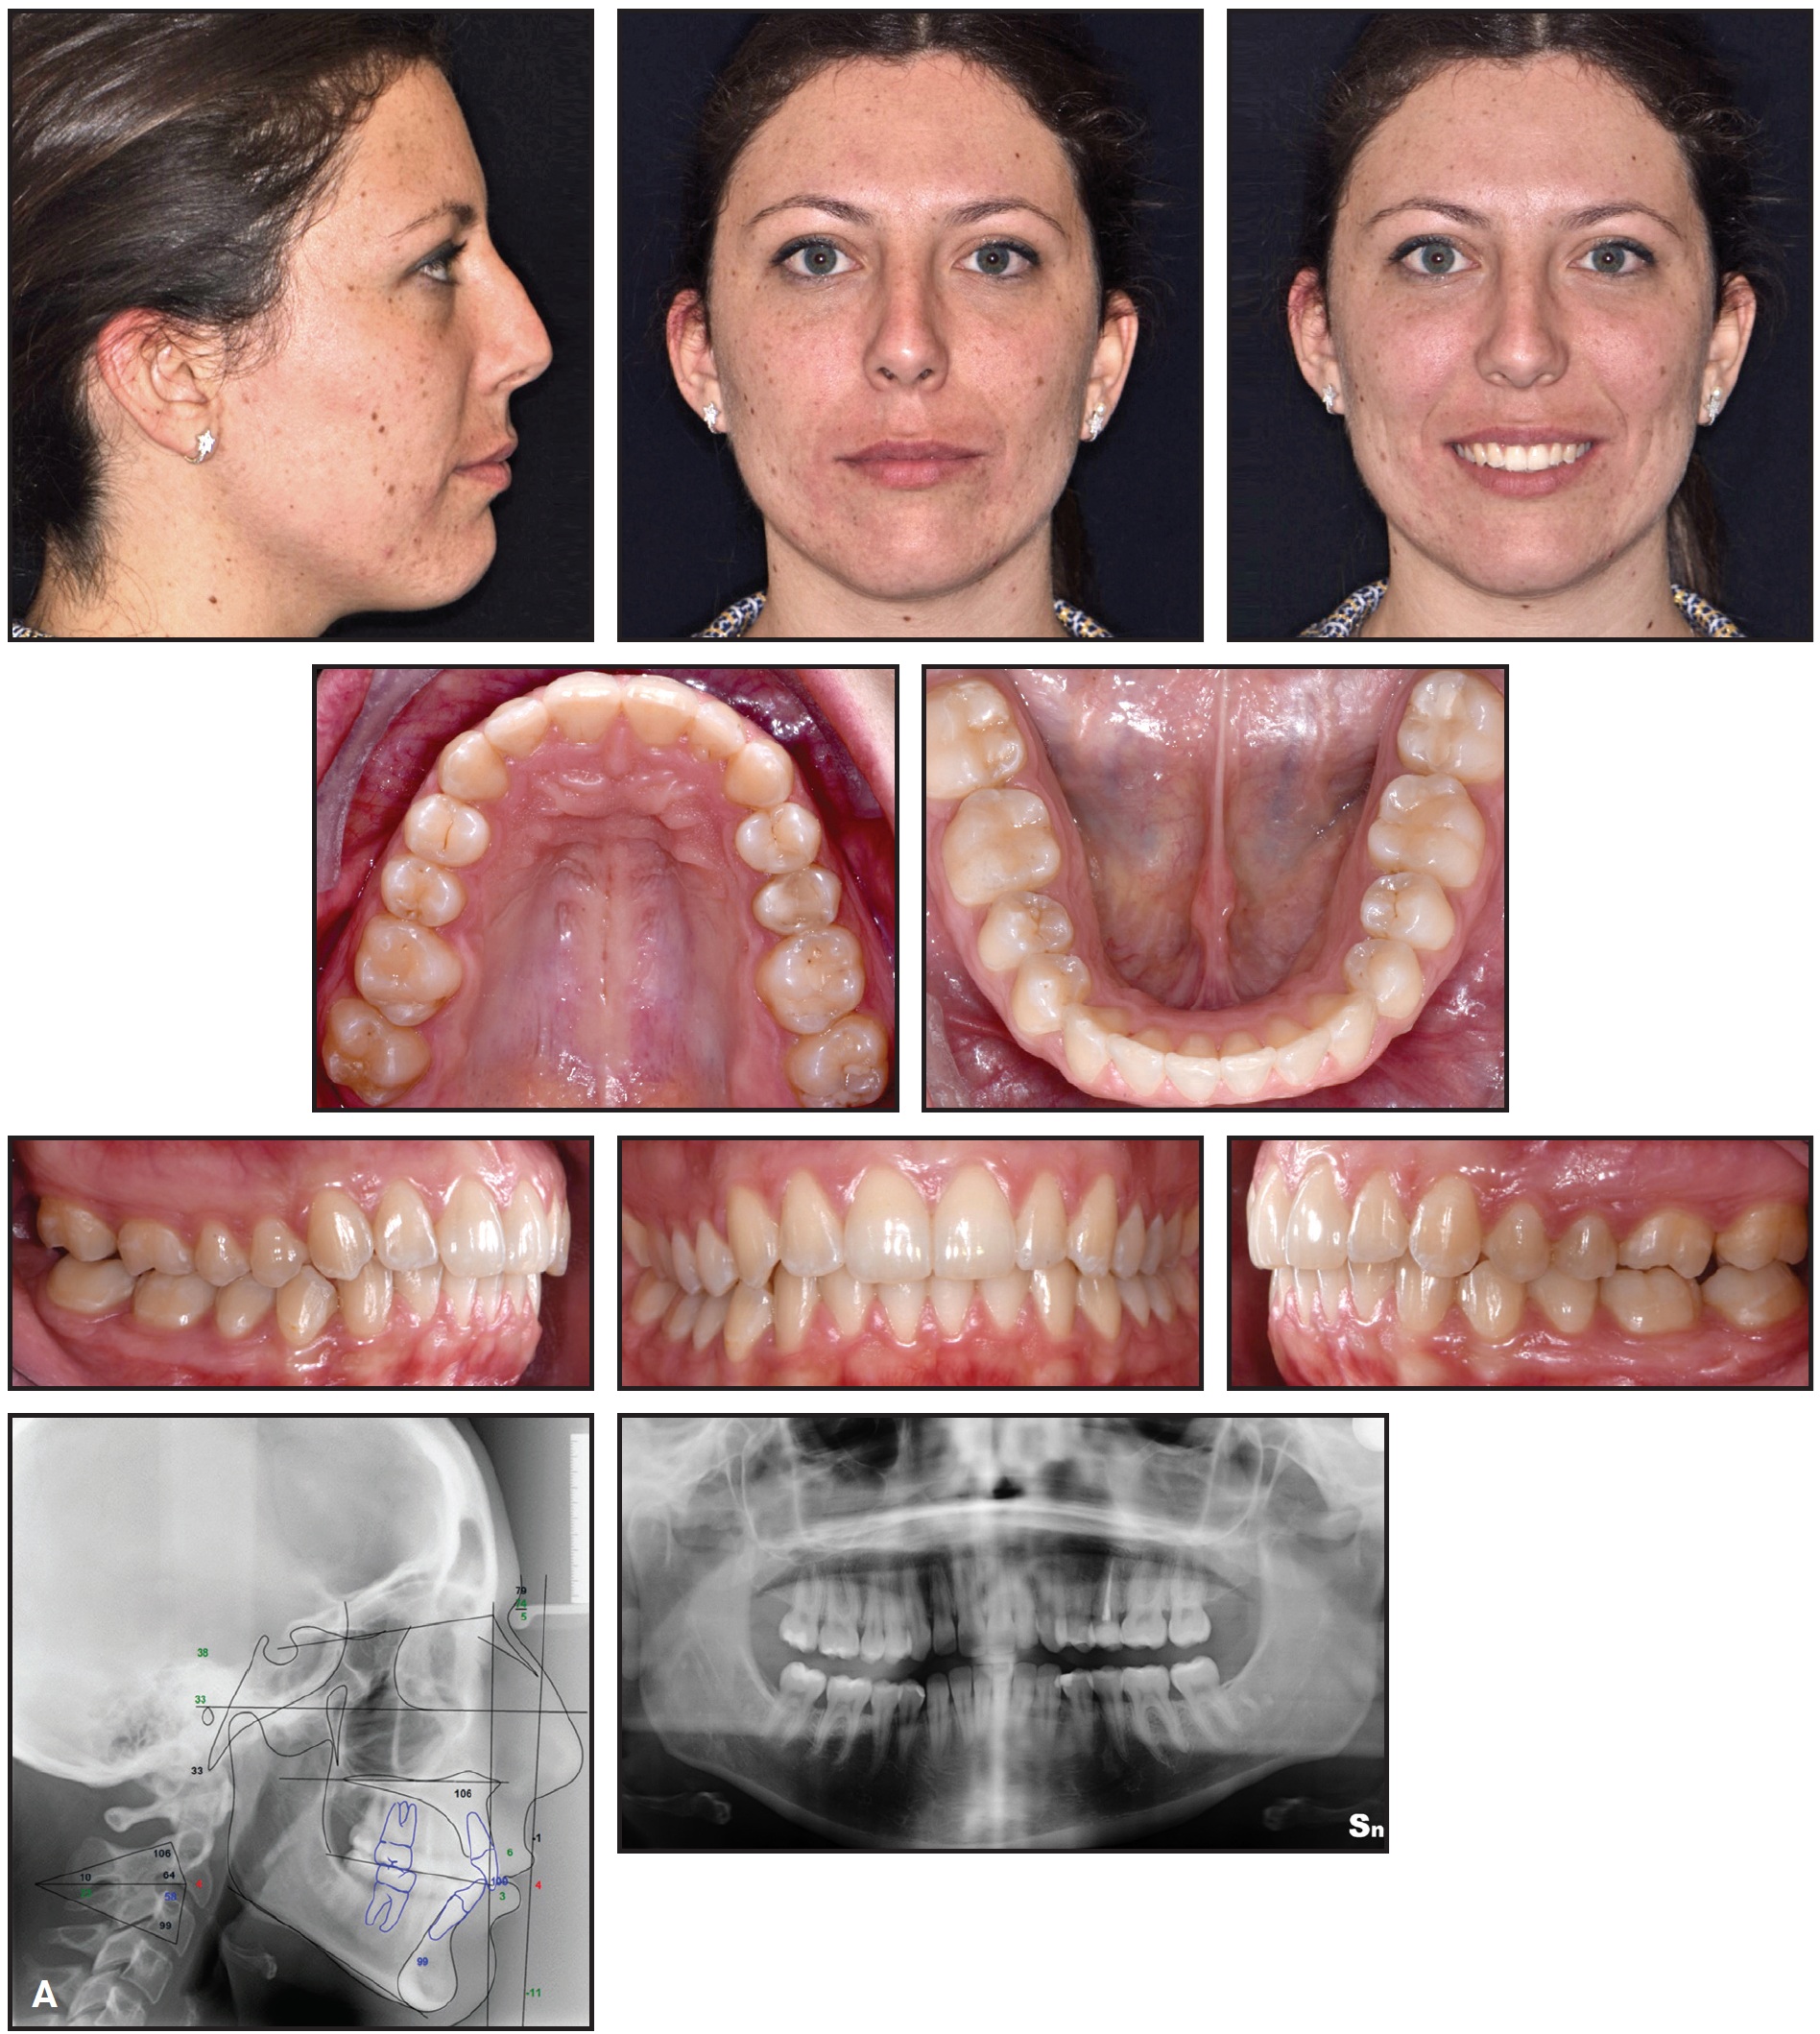

After a total 10 months of treatment, the objectives had been achieved (Fig. 8A).

Fig. 8 A. Patient after 10 months of treatment (continued in next image).

Both the lip competence and the anterior dental display in smiling were improved. The Class I molar and canine relationships were preserved, the anterior crowding and malalignment were corrected, the midlines were fully centered, and satisfactory overjet and overbite were attained. The scissor bite on the right side was resolved (Fig. 8B.

Fig. 8 (cont.) A. Patient after 10 months of treatment. B. Superimposition of pre- and post-treatment cephalometric tracings.

The post-treatment panoramic radiograph showed good root parallelism with no signs of root resorption or bone defects. Cephalometric analysis confirmed retroclination of the upper anterior teeth and slight intrusion and proclination of the lower teeth (Table 1). The skeletal divergence did not worsen, and a proper vertical facial relationship was maintained.

In the second phase of our treatment, the occlusion and the anterior alignment were improved by clear aligner therapy while the scissor bite was corrected by the fixed component. Comparison of pre- and post-treatment cephalometric tracings showed that only dentoalveolar effects were obtained, including retroclination of the upper anterior segment and intrusion and proclination of the lower anterior teeth (Fig. 8B). The superimpositions demonstrated proper control of the patient’s skeletal divergence.